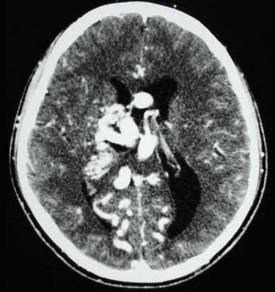

问题 男,32岁,头痛、癫痫,查体发现视乳头水肿,CT检查如图,最可能的诊断为()

选项 A.结节状硬化 B.钙化灶 C.动静脉畸形 D.少突胶质瘤 E.脑囊虫

答案 C